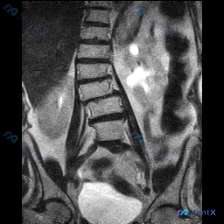

整理了一份腰椎MRI的读片讨论资料,先看冠状位T2加权像的客观表现: 1. 脊柱排列:腰椎向左侧凸(Levoscoliosis),椎体有旋转,中轴线不平直 2. 椎间盘:多节段下腰椎T2信号明显减低(“黑盘”征),提示脱水退变;凹侧(左侧)椎间隙更窄,有挤压 3. 椎体/软组织:椎体边缘有骨赘;骨髓...

整理了一份影像病例资料,大家先看看: 核心影像表现(腰椎MRI T2冠状位): 1. 腰椎序列左侧弯畸形,椎体排列基本连续 2. L2/3、L3/4、L4/5椎间隙不对称性变窄(左侧更甚) 3. 多节段椎间盘T2弥漫性低信号,提示脱水、变性 4. 侧弯凹侧小关节信号及结构紊乱 5. 双侧髂嵴高度不对...

整理了一份腰椎MRI(T2序列冠状位)的影像资料,先给大家说几个关键发现: 1. 脊柱整体形态:腰椎序列向左侧凸,椎体序列基本连续,未见明显单节段严重滑脱; 2. 椎间盘改变:腰椎下段多个椎间盘T2信号减低,椎间隙高度不均匀狭窄,左侧(凹侧)更明显; 3. 椎间孔情况:左侧(凹侧)椎间孔有不同程度狭...

整理到一份腰椎影像分析资料,第一眼很容易被「脊柱侧弯」吸引,但再仔细看会发现一个容易被忽略的「跨学科线索」。 先放核心影像表现(冠状位T2WI): 1. 脊柱序列:腰椎向左侧突,椎间隙左右不等宽 2. 椎间盘:下腰椎(L3-L4、L4-L5为主)T2信号明显减低(黑盘征),部分节段侧向变窄,椎体边缘...